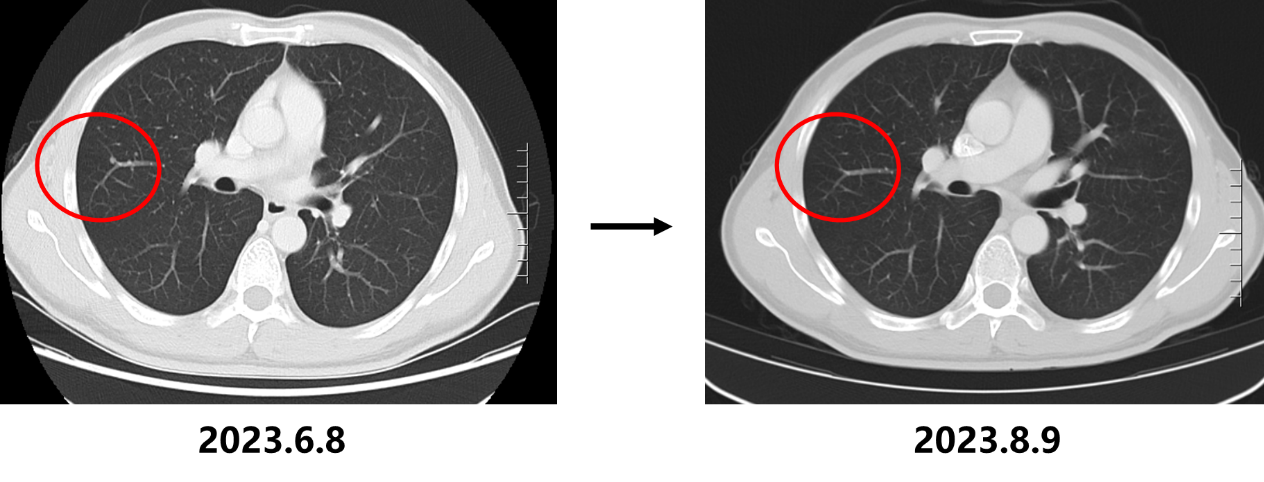

• 2023.8.10复查CT:胃底贲门部胃壁增厚明显改善,肝胃间隙及腹膜后多发淋巴结转移瘤较前缩小(大者短径17mm)、双肺多发转移瘤较前缩小、减少,疗效评估为部分缓解(PR)。

• 2023.9.26复查CT:胃底贲门部胃壁未见明显增厚,肝胃间隙淋巴结较前缩小(长径约0.4cm),腹膜后小淋巴结同前。现双肺未见转移瘤。